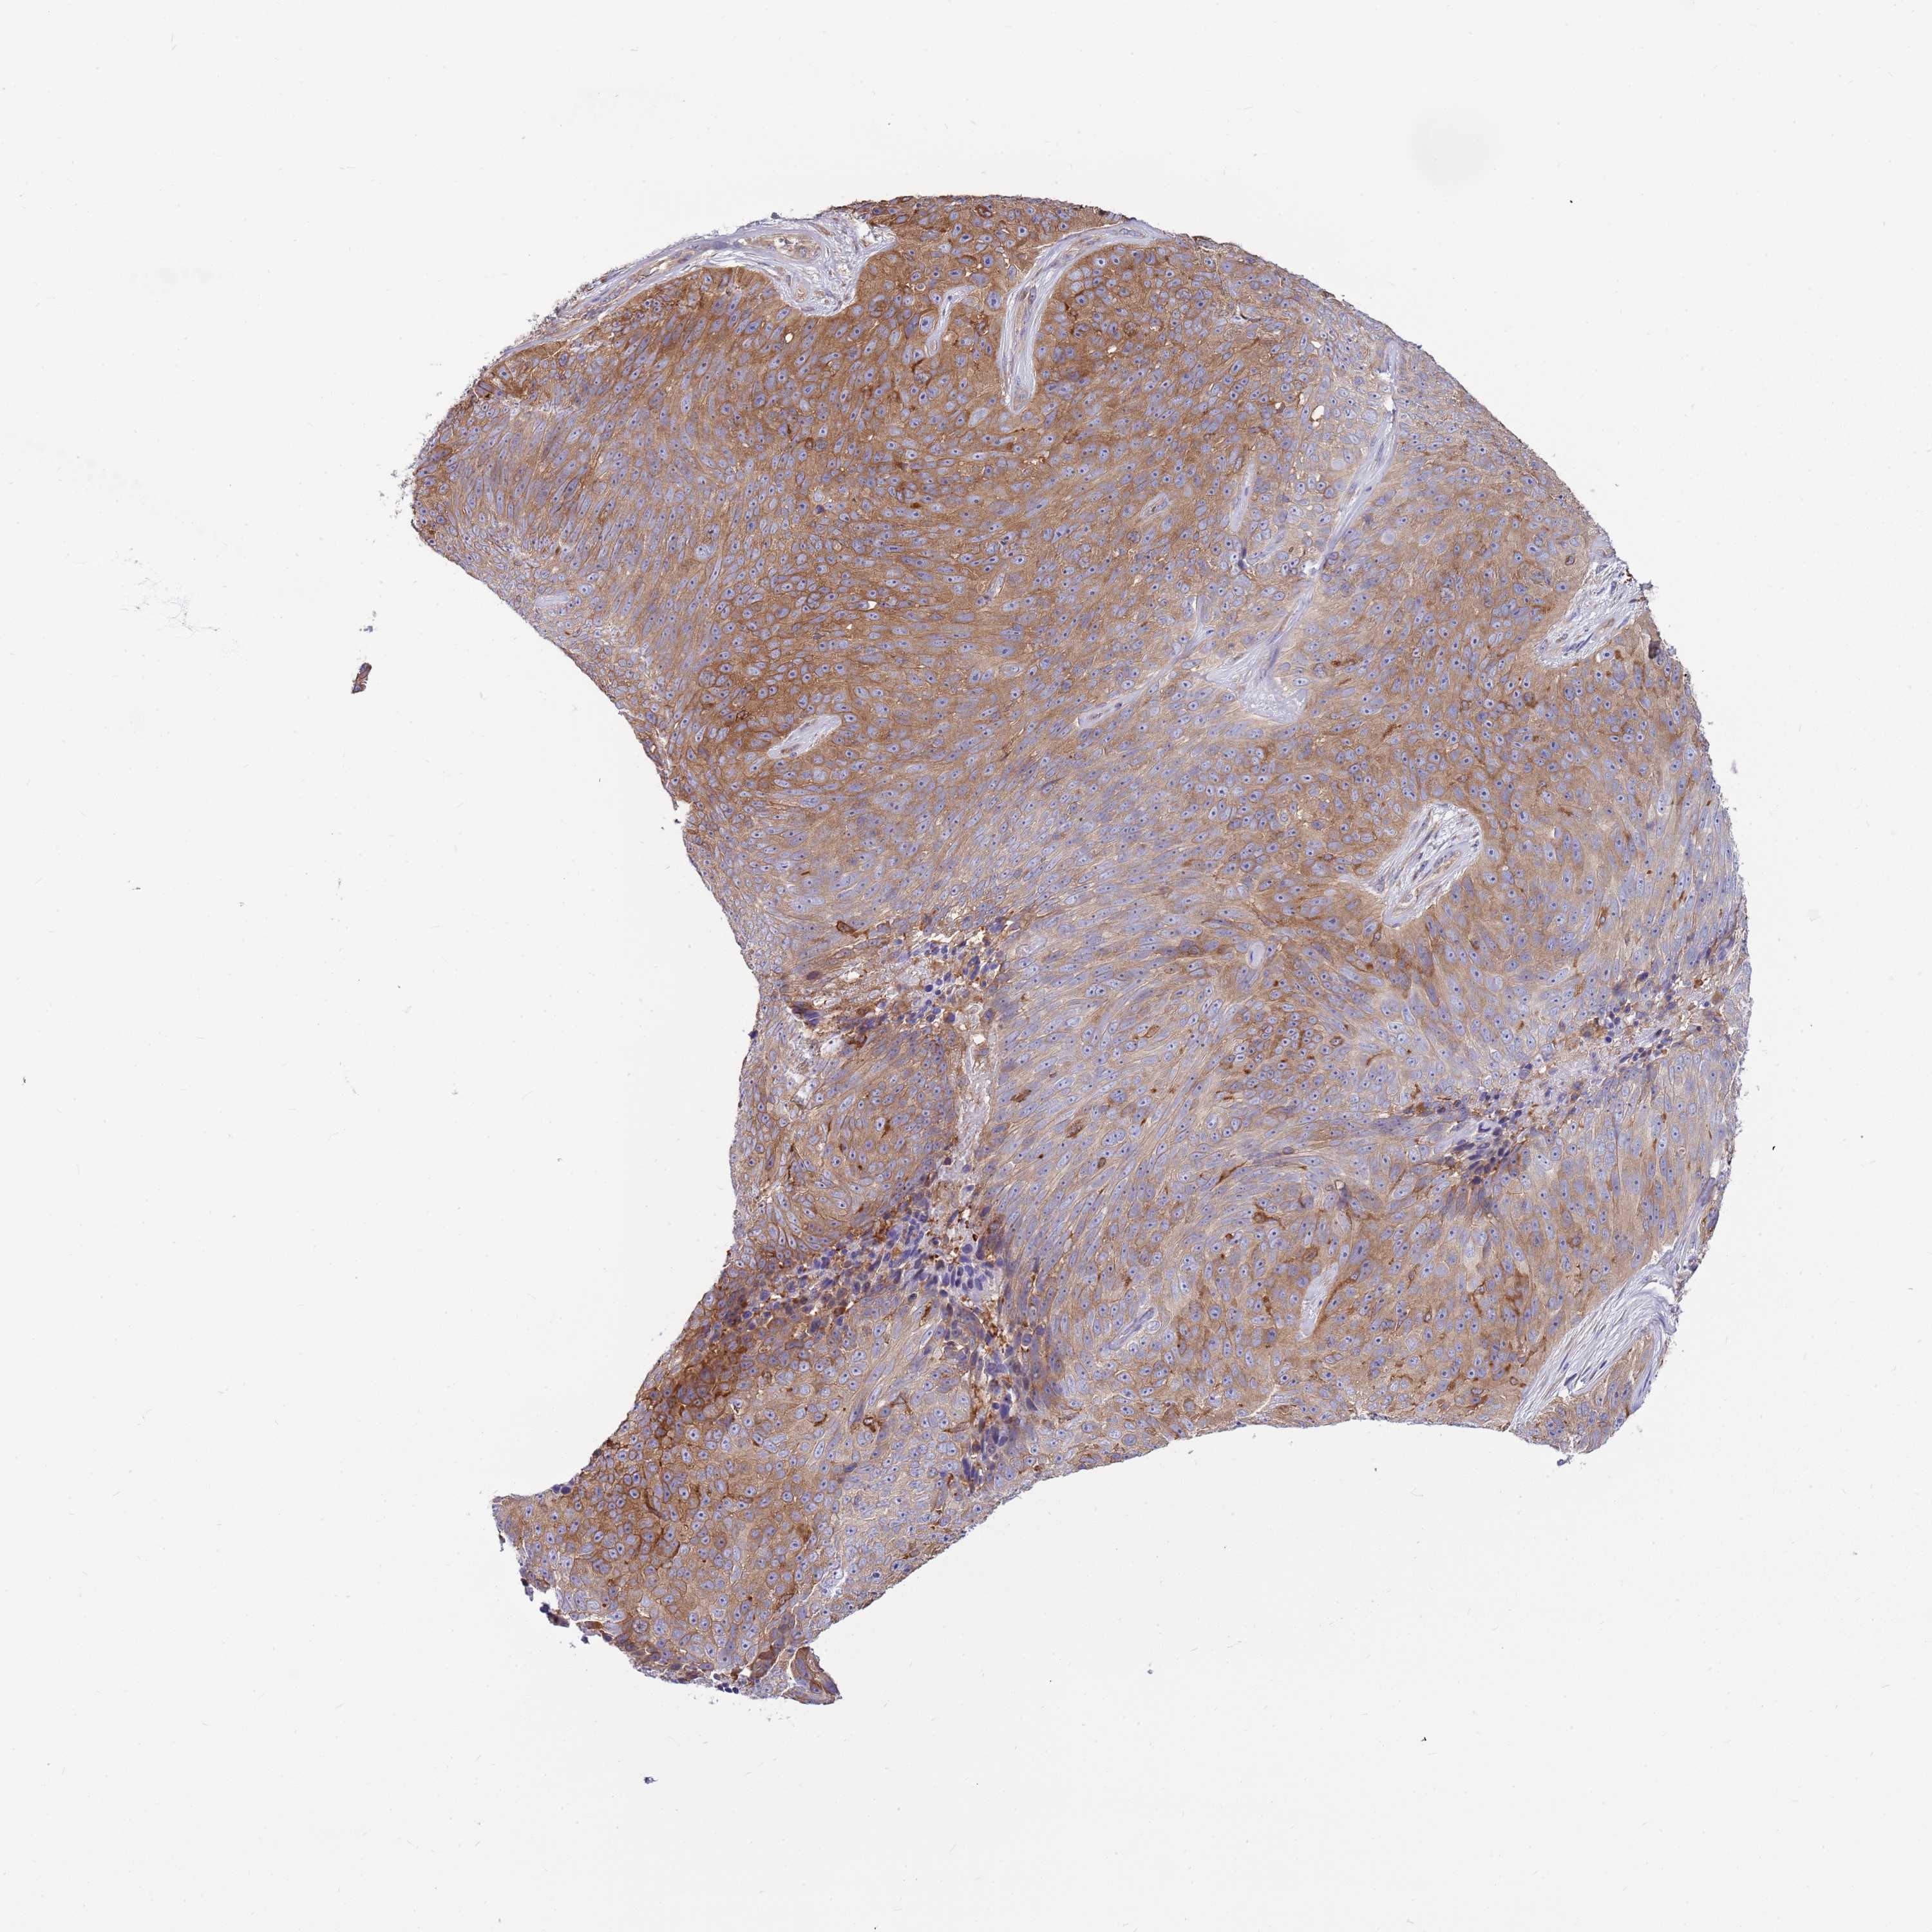

SKIN CANCER - Protein expressioni

A mouse-over function shows sample information and annotation data. Click on an image to view it in a full screen mode. Samples can be filtered based on level of antibody staining by selecting one or several of the following categories: high, medium, low and not detected. The assay and annotation is described here.

Each image is clickable and will lead to virtual microscopy that enables deeper exploration of all samples and also displays staining intensity scores, fraction scores and subcellular localization as well as patient and tissue information for each sample.

Antibody HPA041506

High

Intensity

Quantity

Location

Basal cell carcinoma